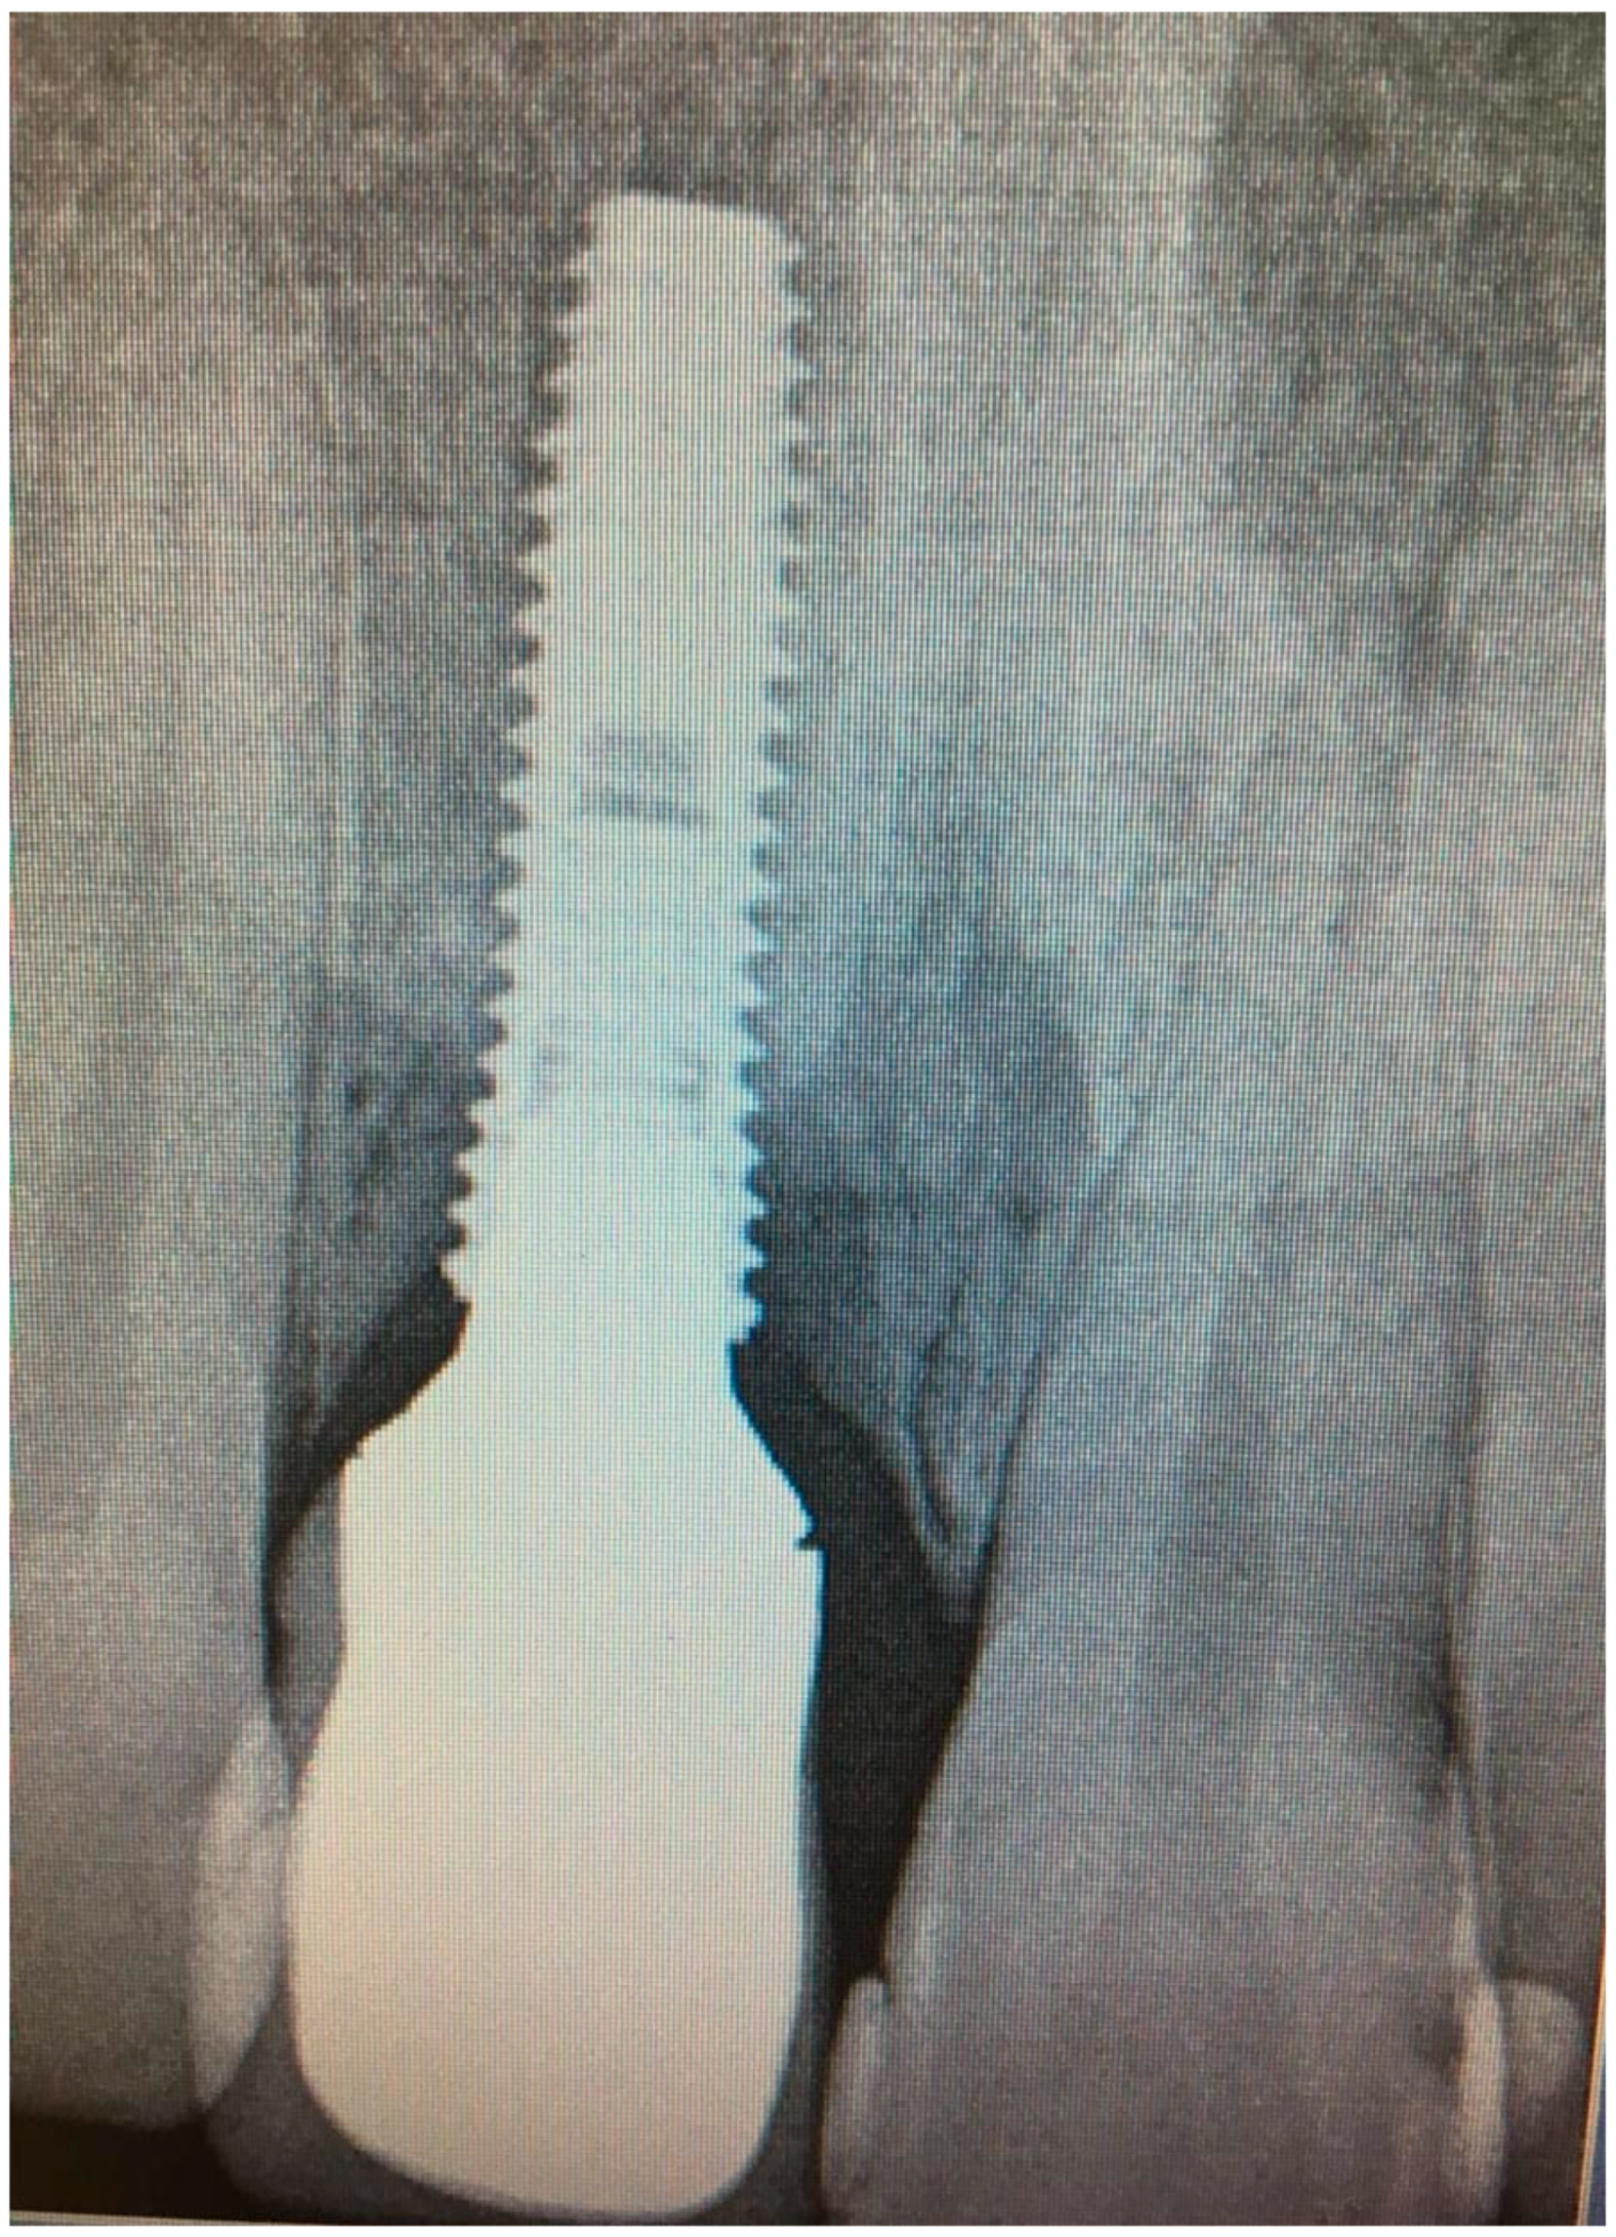

Figure 2.

X-ray of dental implant area before treatment.

Clinical examination revealed that the patient was rehabilitated through one crown with gum mask cemented on one dental implant placed in 1.1 position and had the presence of local inflammation (with evident redness and swelling) with significant soft tissue retraction. By the use of one plastic probe (Hawe Perio-Probe™, Kerr Corporation, Orange, CA, USA), we found deep (more than 4 mm) probing depth in all sites of 1.1 position of dental implant improving on radiological investigation, with intensive bleeding on probing and suppuration (Figure 6).

Figure 6.

X-ray of patient before treatment in position 1.1 of dental implant.